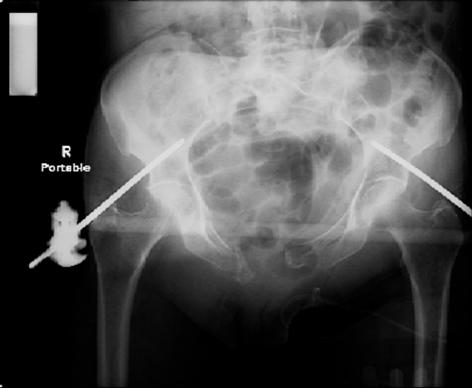

attached are images of a 70 year old female after peds versus car. her own car ran her over.

injuries are limited to the pelvis. left rami open and visible in a 10cm vertical laceration just lateral to left labia majora. wound is grossly clean. no vaginal and no urinary issues. CT scan shows widening of both SI joints anteriorly but I think this is vertically stable pattern.

pt treated that night with I/D and supra-acetabular frame to close the ring. consideration was given for SI screws bilateraly, but given time of night and other factors decision made not to proceed.

so the question is what next operatively if anything? concerns are infection, nonunion anteriorly and possible incompetence of the pelvic floor which may lead to prolapse issues. right rami are comminuted and plating may entail ilioinguinal approach to extend plate laterally to right iliac wing. retrograde screw up right rami is an option but I am not convinced it will add much. adding SI screws very doable, but major concern is restoring anterior ring. so far wound is clean and closed over a drain, and I have no plans to open it back up and wash again.

maintaining pelvic alignment in ex-fix in 70 yo female for any length of time may be challenging.

any thoughts? would anyone plate the pubic symphysis to close the gap and leave the more lateral rami fractures alone? the most recent pelvic case on this website involved pts with suprapubic catheters and antibiotic options including resorbable beads. I wonder how many people would plate and place antibiotic beads. thanks.